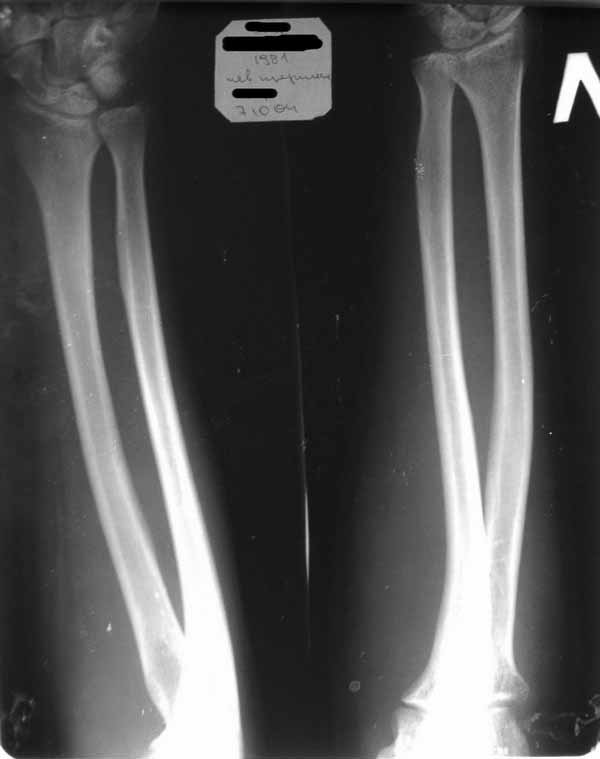

Уважаемые коллеги! Требуется ваша помощь. На консультацию обратился пациент 30 лет с

Пассивные в полном объеме. Со слов имела место некая родовая травма. К тому же отмечается незначительный

дефицит иннервации n.radialis (снижение ╚ силы ╩ разгибателей-сгибателей в кистевом

суставе и отведения 1 пальца; неврологи никакого специфичного лечения не назначают). Также

имеется контрактура локтевого сустава: сгибание в полном объеме, разгибание 150 градусов,

супинация в пределах 7 градусов. Функция конечности в принципе устраивает. Скелетных травм

в анамнезе нет. Вопрос: есть ли смысл заниматься какими-либо реконструкциям на плечевом

суставе и как можно улучшить функцию скомпрометированных суставов? Заранее всем

благодарен